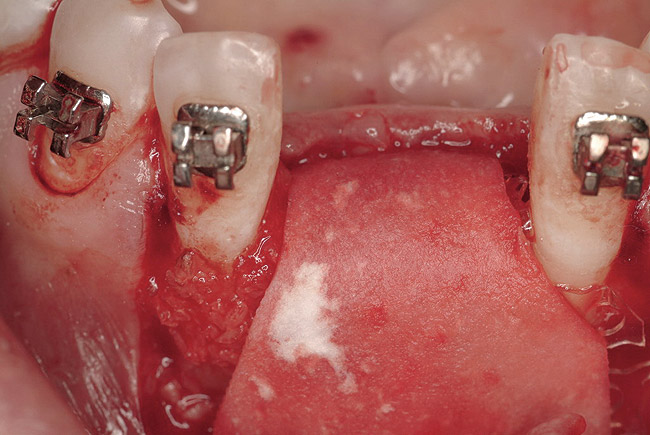

Figure 3  Pre-extraction situation. Tooth Nos. 24 and 25 were planned for extraction, and simultaneous ridge augmentation was planned. Implant placement in these two positions at the conclusion of active tooth movement was also planned.

Figure 3

The patient, a 39-year-old woman, presented at the inception of multidisciplinary therapy. Prior to starting comprehensive orthodontic treatment, it was determined that tooth Nos. 24 and 25 were deemed hopeless (Figure 3). Cross-sectional views obtained from cone-beam computer tomography (CBCT) demonstrated deficient labial and lingual cortices at the time of presentation (Figure 4 and Figure 5). Full-thickness flap reflection and delicate extractions were done, utilizing periotomes and forceps and taking precaution to avoid unnecessary trauma and further bone loss; tooth Nos. 24 and 25 were removed (Figure 6). Following thorough debridement with ultrasonic and hand instrumentation, the defects were obturated with a mineralized allograft (freeze-dried bone allograft [FDBA], Musculoskeletal Transplant Foundation [MTF] Tissue Bank, www.mtf.org) (Figure 7). For purposes of graft containment, a traditional barrier membrane may have been chosen; however, due to the compression of the overlying flap and an anticipated 6 to 9 months before implant placement was expected to occur, a thin or knife-edge crest ridge anatomy could result in this area. Therefore, a rigid, resorbable mesh was utilized to provide graft containment and space maintenance (Figure 8). This PLGA-composed mesh was trimmed extraorally to the desired size of the defect, then placed in a sterile, warm water bath at 70°C for about 10 seconds. This temporary warming allows for 3-dimensional (3-D) contouring of the flat mesh to the desired shape needed to reconstruct the alveolar ridge. To prevent movement of the mesh in situ, it was affixed to the labial cortex with screws composed of the same PLGA polymer. A dermal allograft was placed over the graft site to augment the volume of soft tissue in this area of typically thin keratinized mucosa (Figure 9). The flaps were closed in a tension-free manner after a facial periosteal-releasing incision (Figure 10).